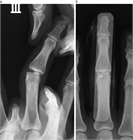

1. 指が物にぶつかって受傷するいわゆる「突き指」には、骨折や靭帯損傷など重度の損傷が隠れている場合がある。

1. 注意深い診察とX線写真撮影により、損傷に応じた適切な治療を行うことが推奨される。